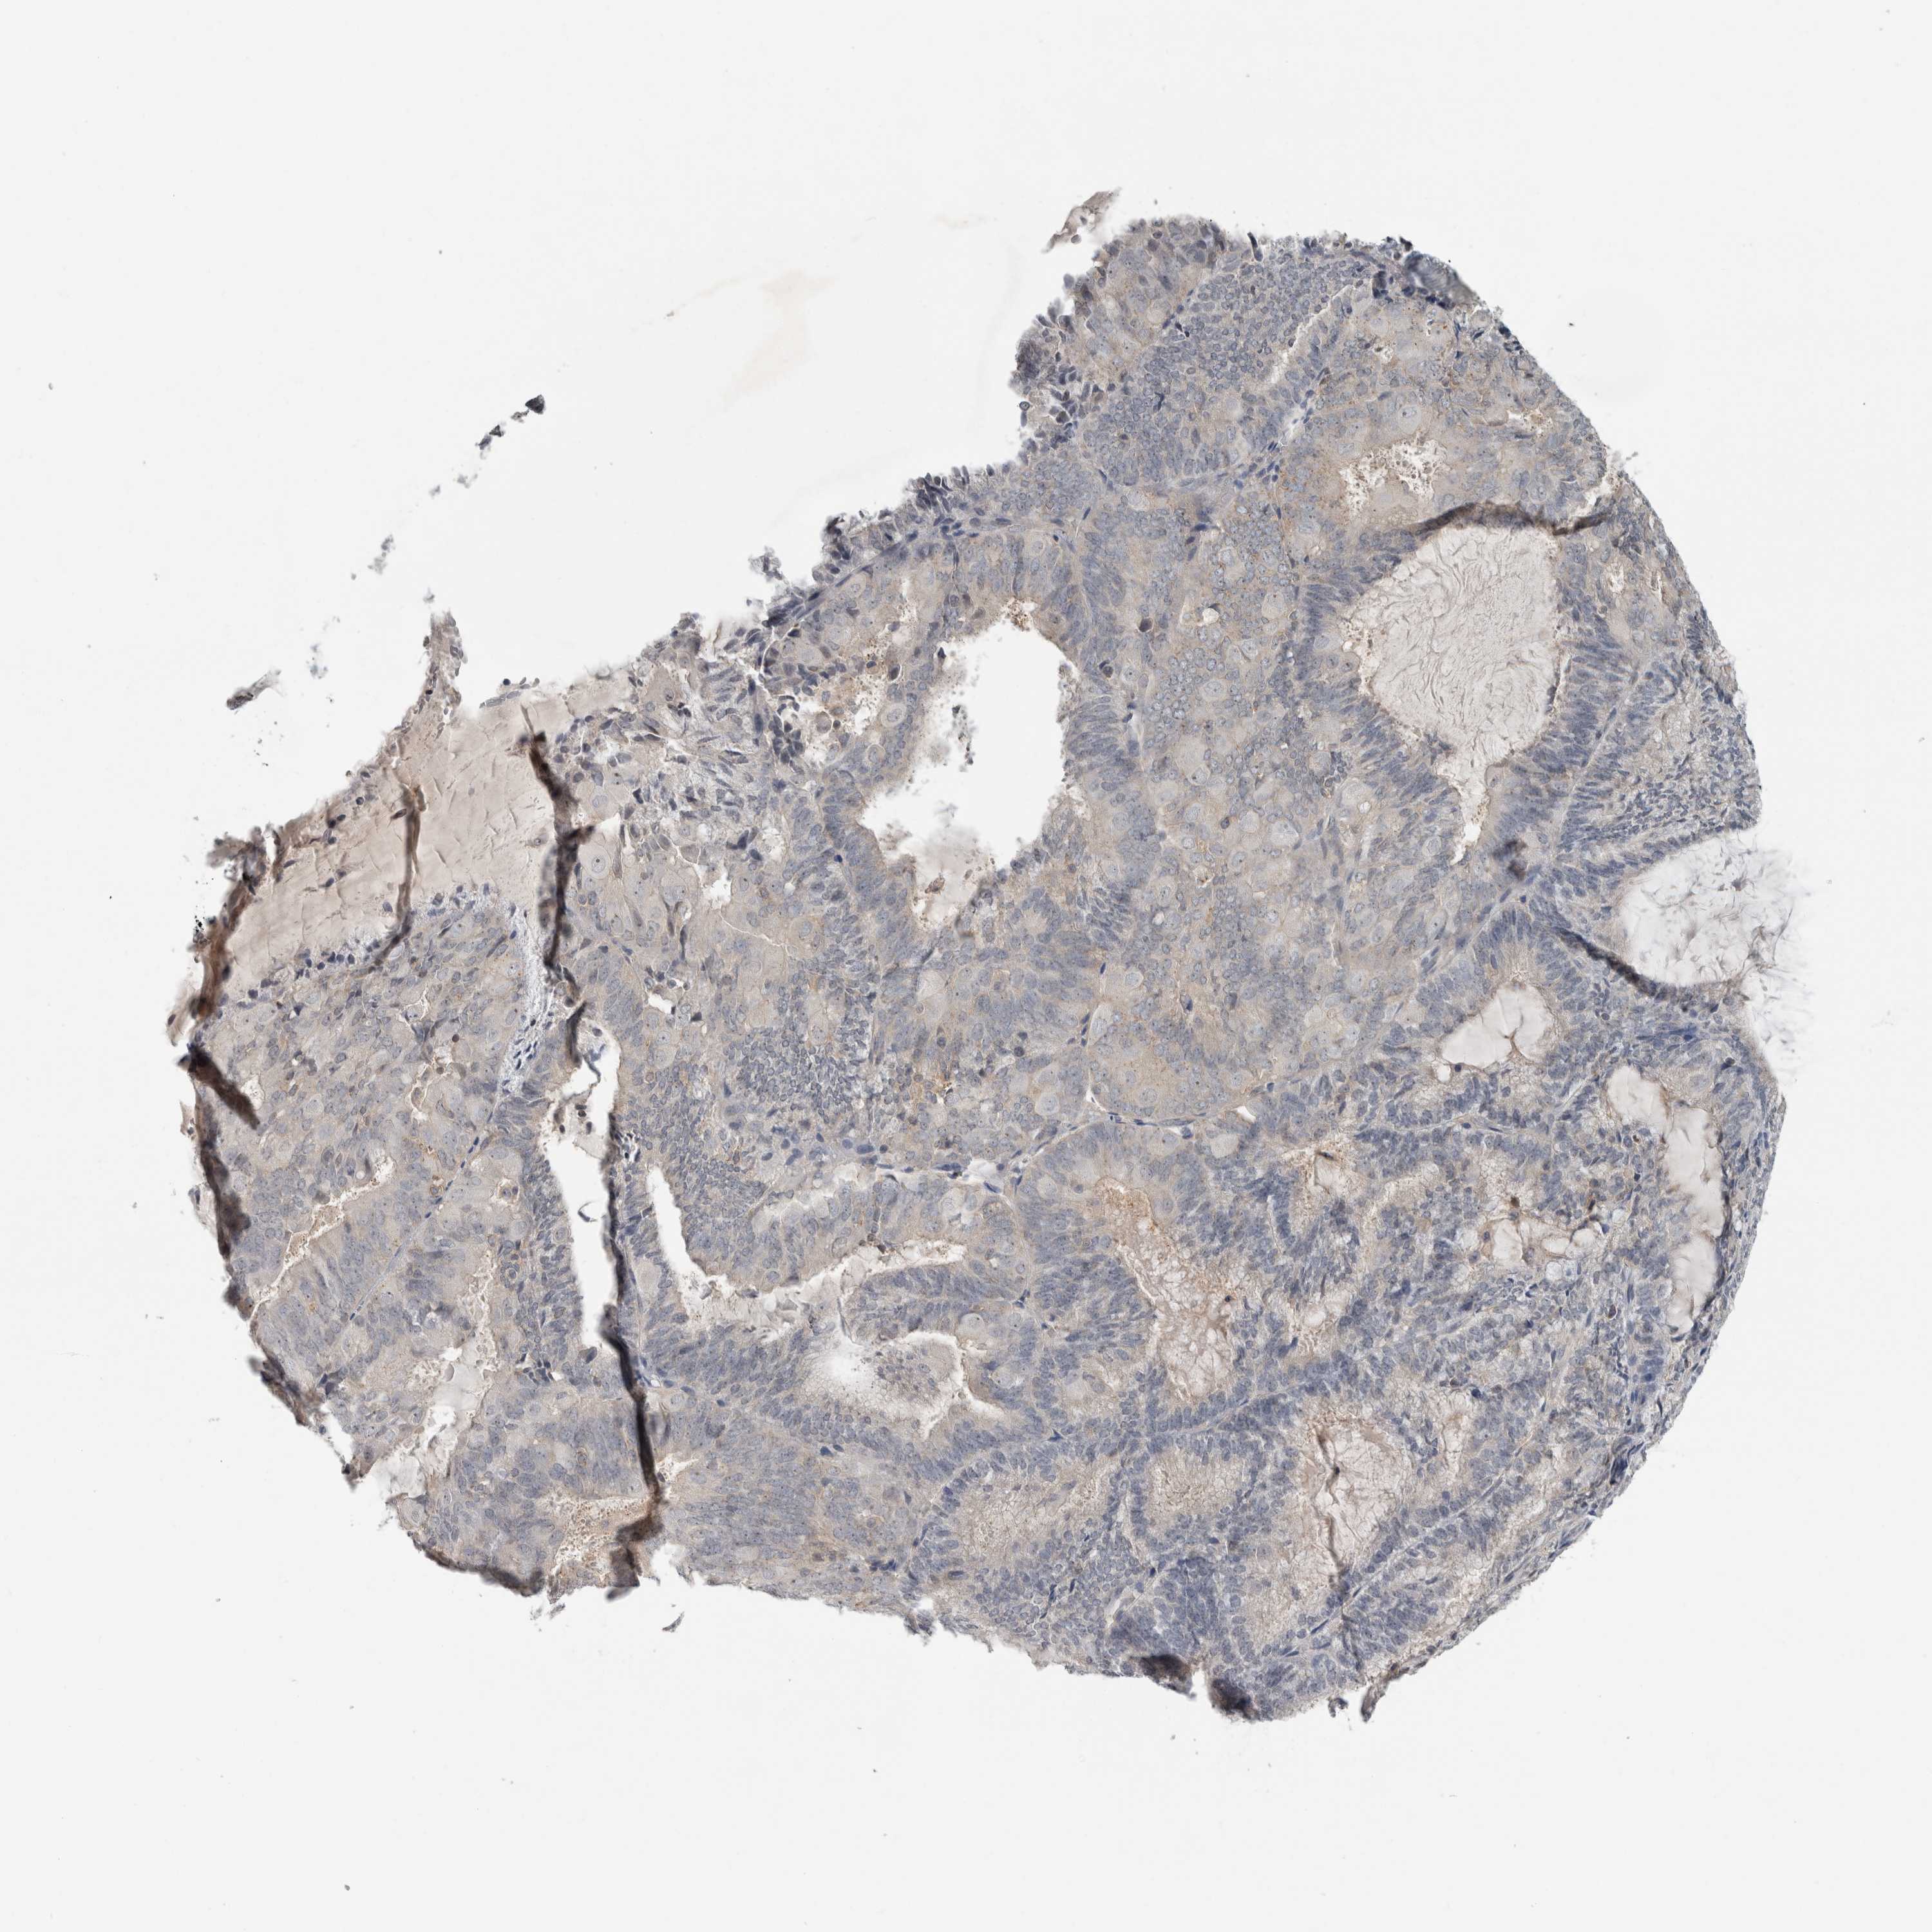

ENDOMETRIAL CANCER - Protein expressioni

A mouse-over function shows sample information and annotation data. Click on an image to view it in a full screen mode. Samples can be filtered based on level of antibody staining by selecting one or several of the following categories: high, medium, low and not detected. The assay and annotation is described here.

Note that samples used for immunohistochemistry by the Human Protein Atlas do not correspond to samples in the TCGA dataset.

Antibody stainingi

Antibody staining in the annotated cell types in the current human tissue is reported as not detected, low, medium, or high, based on conventional immunohistochemistry profiling in selected tissues. This score is based on the combination of the staining intensity and fraction of stained cells.

Each image is clickable and will lead to virtual microscopy that enables deeper exploration of all samples and also displays staining intensity scores, fraction scores and subcellular localization as well as patient and tissue information for each sample.

Antibody HPA019058

Antibody HPA026672

Staining

High

Medium

Low

Not detected

Intensity

Strong

Moderate

Weak

Negative

Quantity

>75%

75%-25%

<25%

None

Location

Nuclear

Cytoplasmic/membranous

Cytoplasmic/membranous,nuclear

Adenocarcinoma, NOS

Adenocarcinoma, metastatic, NOS